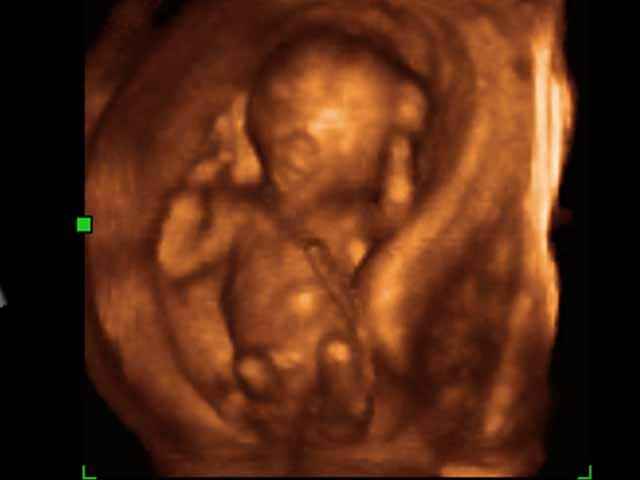

3D First Trimester Ultrasound Scan Photos